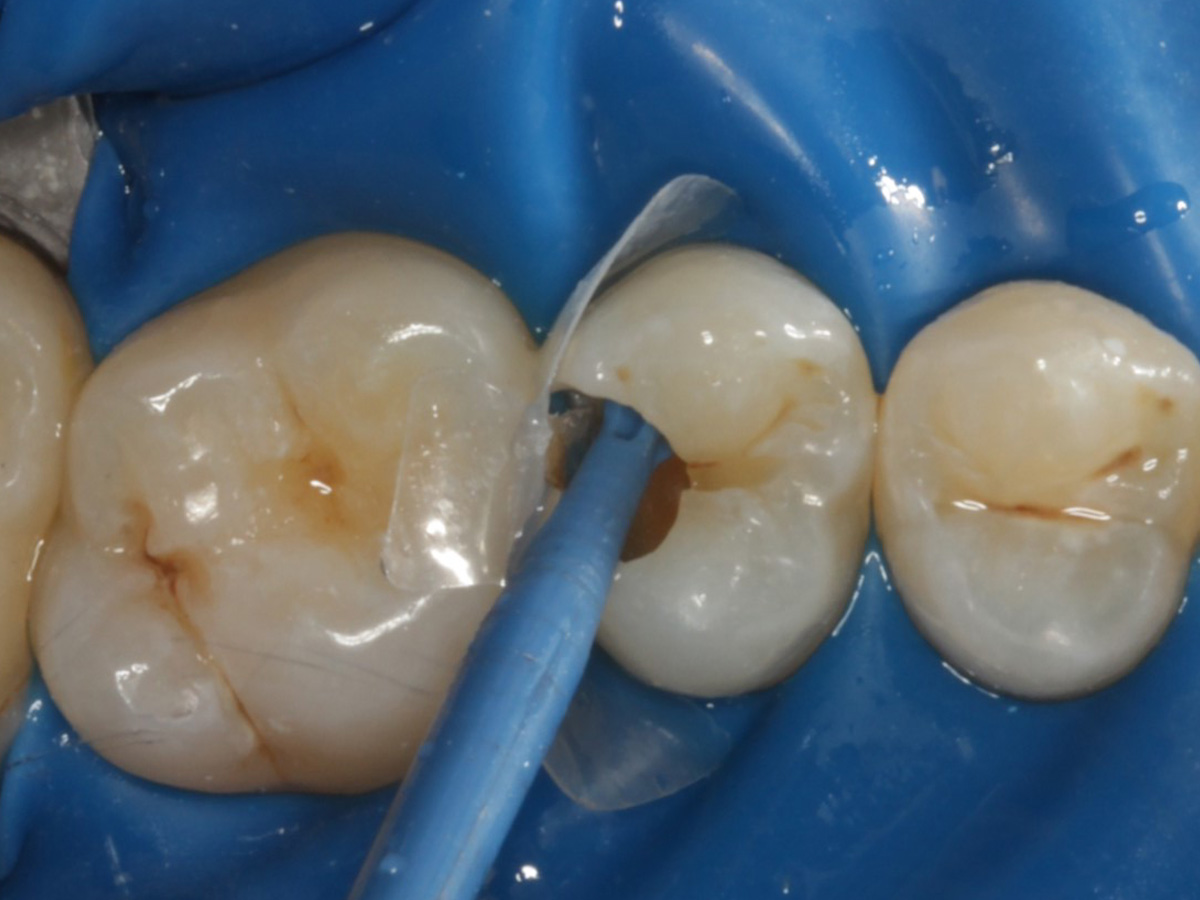

Abbildung 5

Defektdarstellung